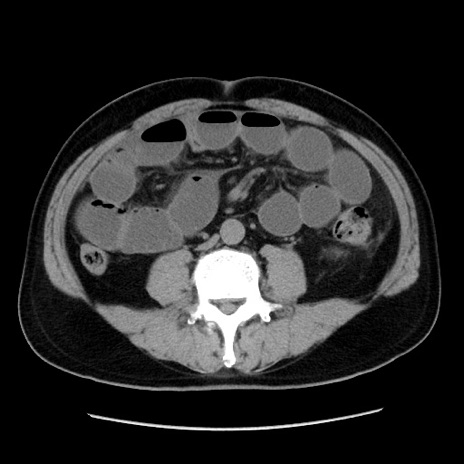

症例16(横断像)

【症例】 70歳代男性

【主訴】 腹痛、嘔吐

【現病歴】 約1ヶ月前より間欠的に腹痛と嘔吐あり、当院消化器内科を受診したところCTで多発する肝臓のLDAを指摘され、精査中であった。以降は消化器症状は安定していたが、2日前より嘔気と腹痛があり、同日より排便・排ガスが消失した。改善認めず、 本日、救急外来を受診した。

【既往歴】 大腸ポリープ切除後。

【身体所見】意識清明・会話良好、BT 36.3℃、BP 127/80mmHg、 P 80bpm、腹部:膨満あり、平坦・軟、上腹部正中および下腹部正中に圧痛あり、反跳痛なし、筋性防御なし。

【データ】WBC 7200、CRP 0.77